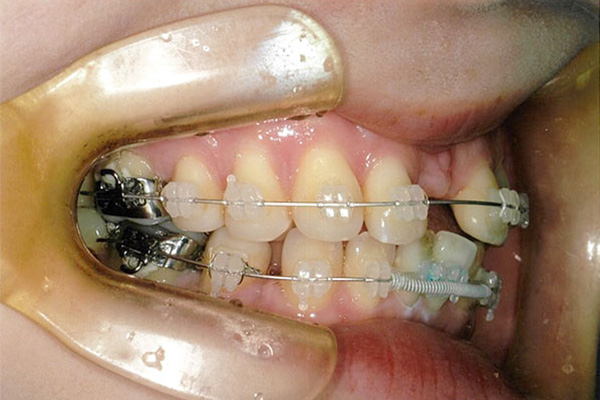

2年1ヶ月後